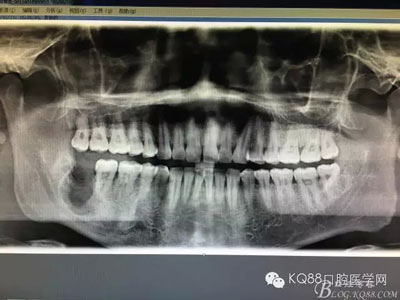

患者、常xx、男、26歲,主訴:右側(cè)下頜牙床腫痛不適數(shù)月。??茩z查:48未見萌出,頰側(cè)骨質(zhì)略有膨隆。捫診輕微不適,無乒乓感,牙齦色澤基本正常,探針無盲袋。全景片檢查:48埋伏水平阻生,其牙冠下方有一囊性陰影,界限清楚,大小約1.5x1.1cm。CBCT檢查:囊性病變已經(jīng)導(dǎo)致部分頰舌側(cè)骨板缺失。診斷:48埋伏阻生伴發(fā)囊性變。治療計劃:建議拔除48,并摘除下方的囊腫?;颊咄庵委熡媱?,簽知情同意書。

圖2.術(shù)前的CBCT檢查:48下方頜骨橢圓形囊性陰影,下方接近下頜管。

圖3.這張重建的全景片,似乎48就漂浮在囊腔上方,由此感覺48拔除如同探囊取物一般。

圖18.術(shù)后全景片影像檢查:頰舌側(cè)骨缺損接近下頜神經(jīng)管,會不會出現(xiàn)骨折的可能,有點(diǎn)糾結(jié)??!